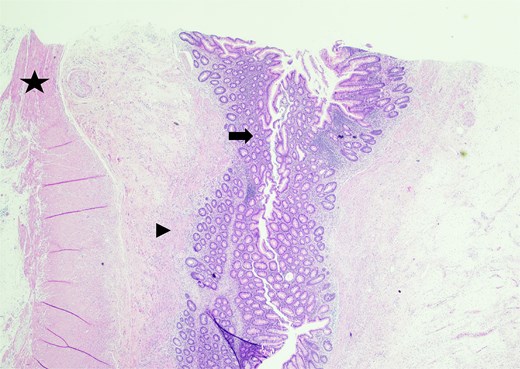

In the operating room, multiple adhesions from the patient’s prior colostomy site and colon resection were noted. The appendix was found to be dilated, acutely inflamed, and hyperemic, consistent with the suspected diagnosis of acute appendicitis. Adhesions from the appendix to the abdominal sidewall were dissected bluntly, pulling the appendix to a more medial position. The harmonic surgical device was used to divide the appendix mesentery and the gastrointestinal anastomosis (GIA) stapler with a blue load was used to divide the appendix from the base of the cecum. Final pathology showed an intact vermiform appendix measuring 6.5 × 1.5 cm with 3.2 × 2.5 × 1.6 cm portion of the attached mesoappendix. On gross examination, tan-pink hemorrhagic serosa with minimal adhesions and no exudate was noted. Sectioning of the specimen revealed a 0.5-cm in diameter lumen filled with a moderate amount of hemorrhagic purulent fecal material and at the distal tip, an intact diverticulum with wall measurement up to 0.2 cm in average thickness (Figs 1 and 2).

Sectioning of the intact vermiform appendix, top portion, showing the muscularis propria (star), muscularis mucosa (arrowhead), and colonic mucosa (arrow).